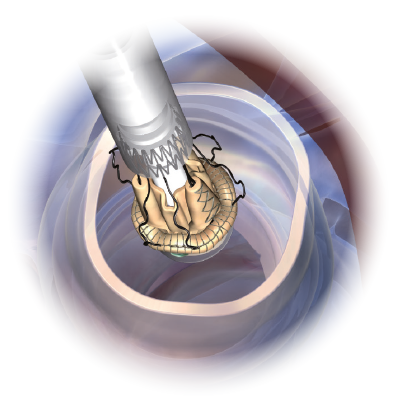

Designed for MICS

Perceval Plus RelyON System and Minimally Invasive Cardiac Surgery were made for each other thanks to the sutureless design of the valve and the length and diameter of the new Deliver System. The System allows for minimized incision,11,15 maximized visibility11,12, faster learning curve14,15 and a reduced manipulation of the aortic root.11,15,16

Minimized incision11,12

Thanks to the unique collapsible profile and sutureless design of the valve and the design of the Delivery System, Perceval Plus RelyON System allows a reduced incision size and less surgical trauma.2,11,17

Maximized visibility during implantation11,12

The collapsible profile of the valve and the small diameter of the Delivery System allow the surgeon full visibility of the annulus and of the anatomical structures during implantation and deployment for great confidence and fast, precise positioning at the implantation site.2,8

Precise

The RelyON Delivery System delivers Perceval Plus with a single movement of the hand allowing to maintain a firm hold on the device, which in turn facilitates a precise positioning of the valve in the aortic root.

Optimized for MICS procedures

The design of the Delivery System is optimized for MICS. Both the length and the small diameter of the shaft, together with the collapsible design of Perceval Plus, allow for a minimized incision and facilitated access to and visualization of the implantation site.